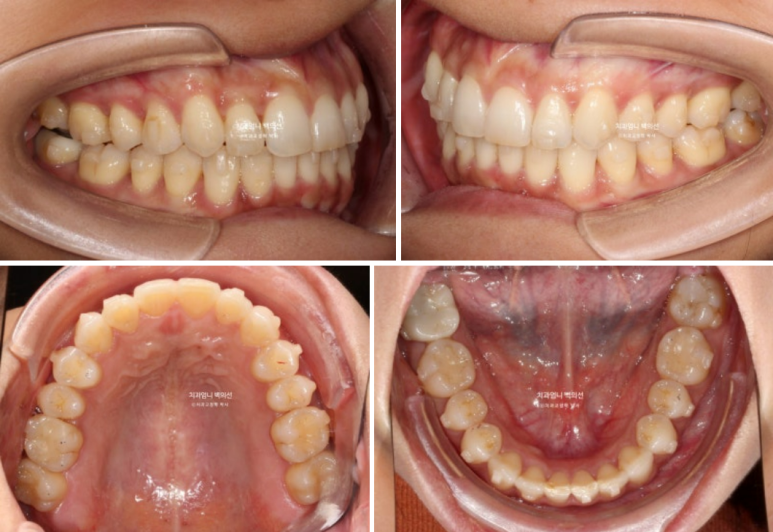

24년 9월부터 25년 1월까지 5개월간 추가장치를 다 낀 모습입니다.

비로소 덧니는 완벽히 제자리를 찾았지만

여전히 약 1mm 가량의 위 아래 중심선 불일치가 보여 환자분 기준 우측 가운데 앞니의 치축이 미세하게 기울어져 보입니다.

환자분도 만족하고 지금도 충분히 좋지만 앞니 중심선을 좀더 일치시키고 치축이 약간 기울어져 보이는 앞니 하나를 위해 2번째 추가장치 제작에 들어갑니다.